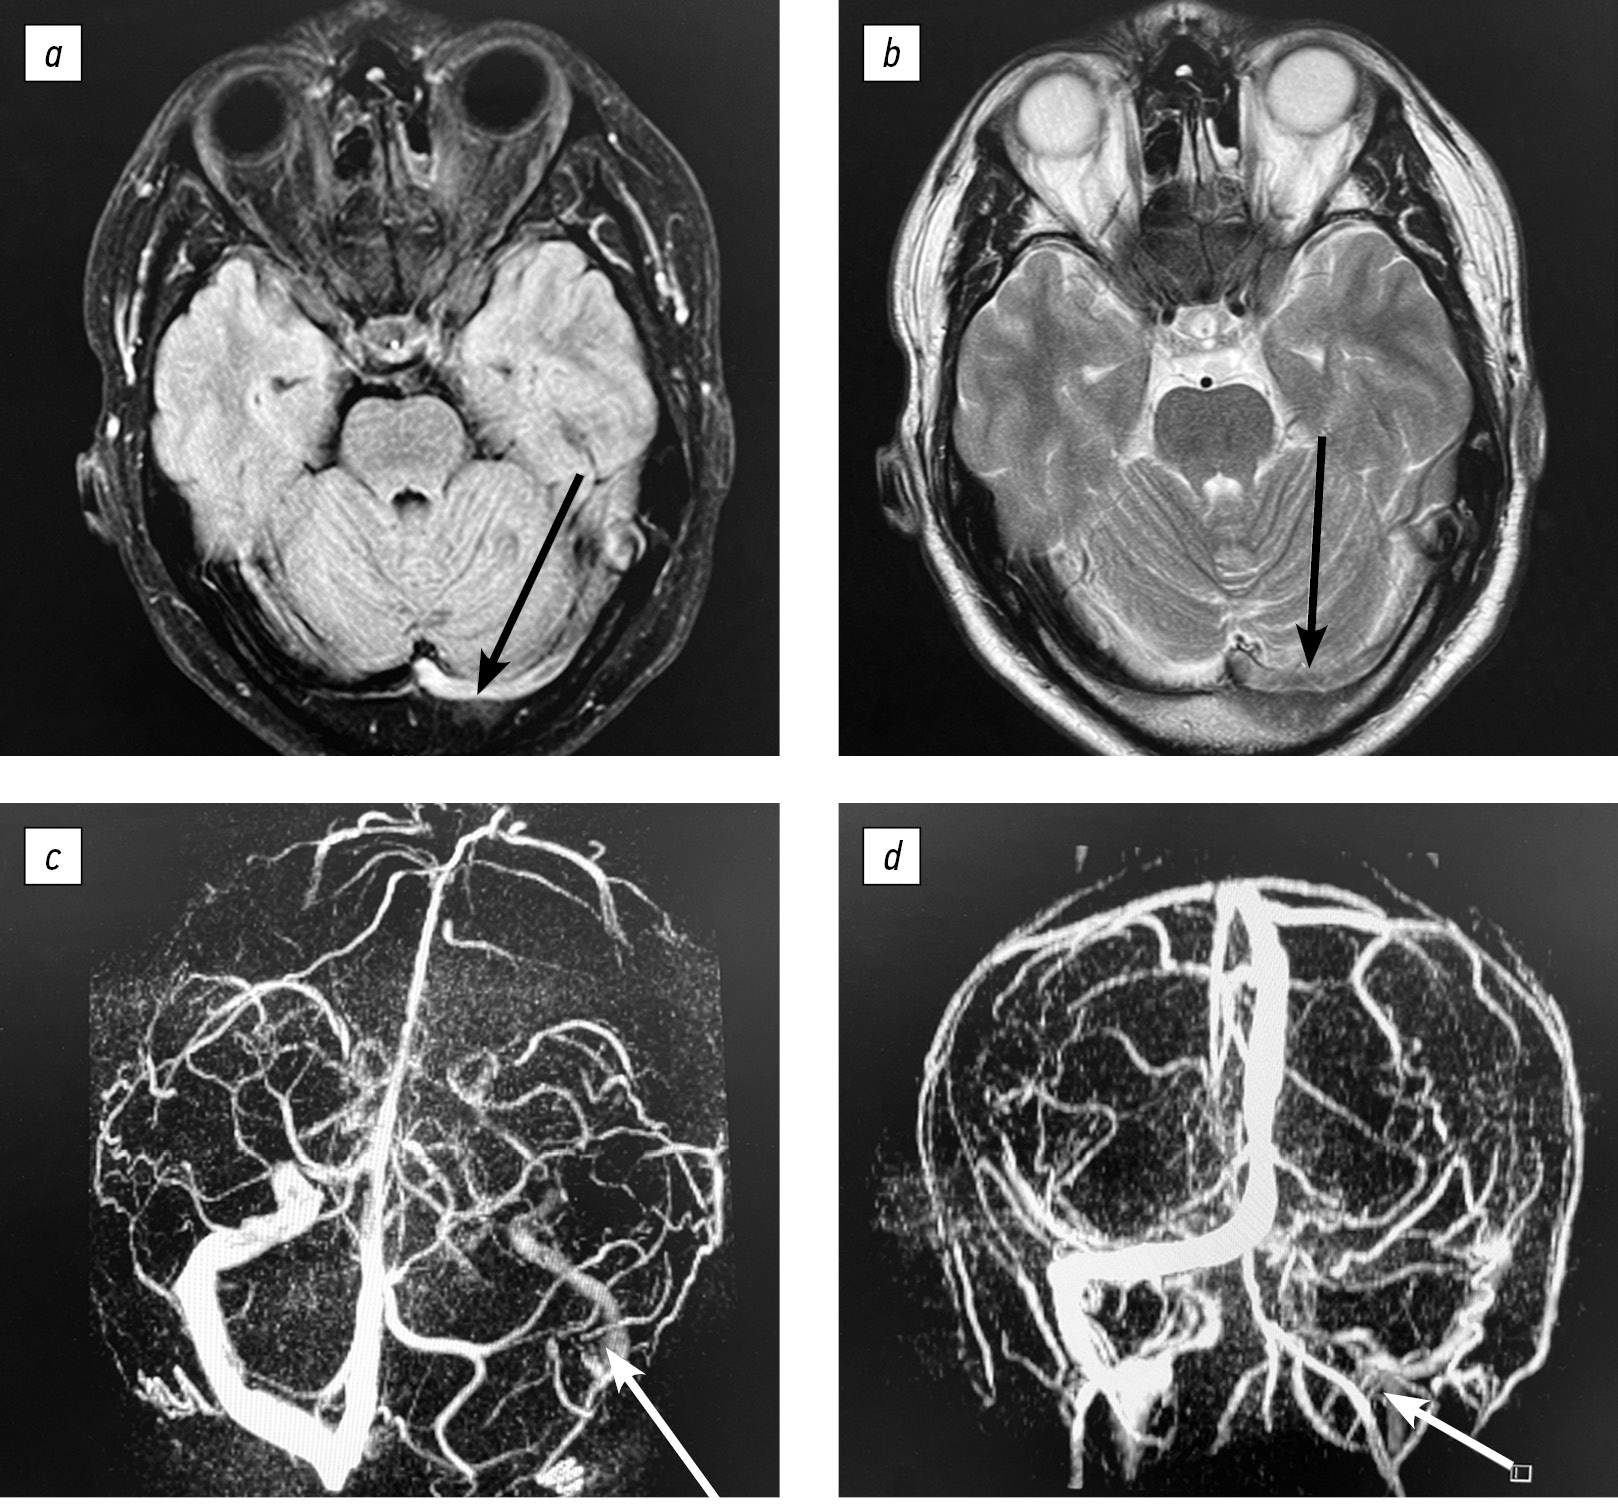

На рис. 2, 3 представлены данные магнитно-резонансной томографии головного мозга и магнитно-резонансной веносинусографии пациента 34 лет до и на фоне антикоагулянтной терапии (через 6 мес.).

Рис. 3. Магнитно-резонансная томография головного мозга и магнитно-резонансная веносинусография через 6 мес. на фоне приема антикоагулянтной терапии. Сохранен низкий сигнал от левого сигмовидного синуса (b, черная стрелка) и частичное восстановление кровотока в левом поперечном синусе (а, b, белая стрелка).

Fig. 3. Brain magnetic resonance imaging and cerebral venous sinus magnetic resonance imaging at 6 months of anticoagulant therapy: The left sigmoid sinus maintains reduced signal intensity (b, black arrow), while the left transverse sinus shows partial blood flow recovery (a, b, white arrow).